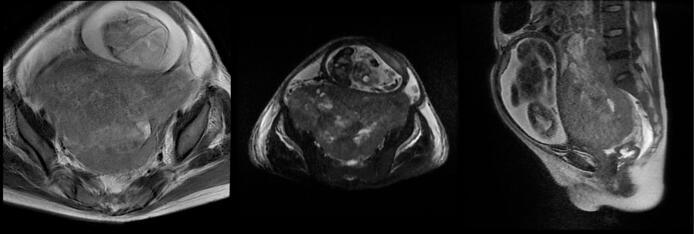

CASE PRESENTATION

We report an exceptional case involving a 22-year-old woman initially diagnosed with a malignant mixed germ cell tumor (MGCT) during pregnancy. Following surgical debulking and chemotherapy, she rapidly developed two distinct secondary malignancies within one year: enteric-type adenocarcinoma and chemotherapy-related acute myeloid leukemia (AML). Despite multidisciplinary interventions, the patient succumbed to disease progression and treatment complications.

我们报告了一例特殊病例,一名22岁女性在怀孕期间最初被诊断为恶性混合性生殖细胞肿瘤(MGCT)。在手术减瘤和化疗后,她在一年内迅速发展出两种不同的继发性恶性肿瘤:肠型腺癌和化疗相关的急性髓系白血病(AML)。尽管采取了多学科干预措施,患者仍因疾病进展和治疗并发症而死亡。